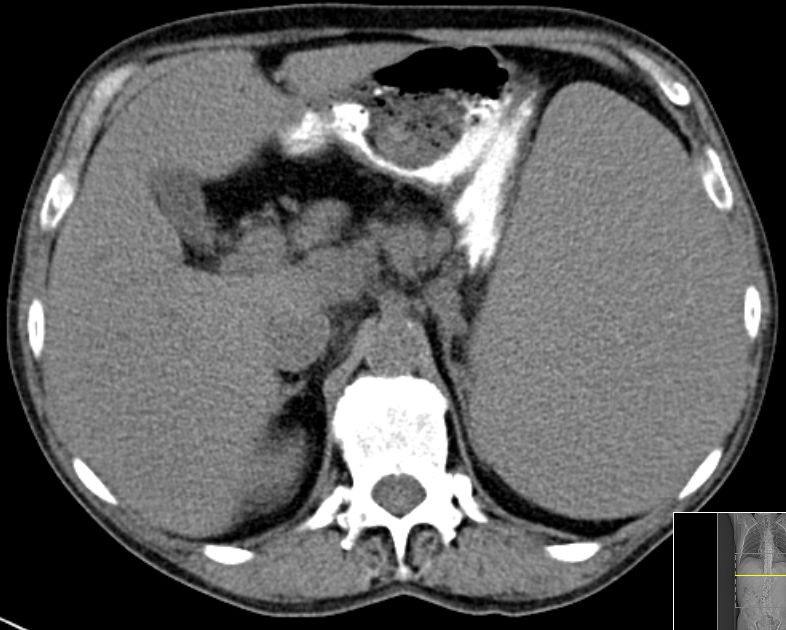

Milz |

59-jähriger Mann mit einem indolenten B-Zell-Lymphom im Stadium IVb.

Ausgeprägte Splenomegalie und Lymphknotenvergrößerung hoch paraaortal. Leuko 11,3, DD 5% gereizte Lymphozyten.![]() |

![]() | ||